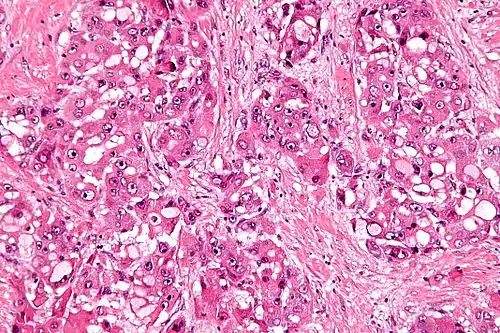

Micrograph of fibrolamellar hepatocarcinoma showing the characteristic laminated fibrosis between the tumor cells with a low NC ratio. H&E stain.

Fibrolamellar carcinoma (FLC) is a rare form of carcinoma that typically affects young adults and is characterized, under the microscope, by laminated fibrous layers interspersed between the tumor cells.[1] It has been estimated that 200 new cases are diagnosed worldwide each year.[2] However, in light of recent advances in our molecular understanding, this has recently been revised to suggest it may be at least ten times more common.[3] FLC, also known as fibrolamellar hepatocellular carcinoma, is different from the more common hepatocellular carcinoma (HCC) in that it afflicts young people with normal liver function and no known risk factors.[1][2][4][5]

The histopathology of FLC is characterized by laminated fibrous layers, interspersed between the tumor cells. Cytologically, the tumor cells have a low nuclear to cytoplasmic ratio with abundant eosinophilic cytoplasm.[1] Tumors are non-encapsulated, but well circumscribed, when compared to conventional HCC (which typically has an invasive border).